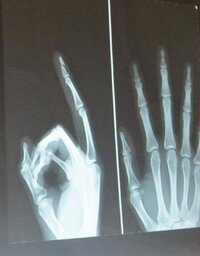

FC東京、右母趾末節骨骨折で代表離脱のMF高萩洋次郎について全治3週間と発表 ドメサカブログ 本田圭佑による新たな問題提起「意外に守備に問題があったりするんじゃないか」 footballnetサッカーまとめ サッカー日本代表 近い将来「ダブル久保」体制に期待 海外サッカー日本人選手速報第五中足骨骨折完治足の指の甲が骨折してから歩ける全治までの経過を写真と共に公開。歩き方は? 今回はみその第五中足骨骨折実体験を元に、記事を書きたいと思います。 骨折したとき、 え、これ本当に治るの? 治るの遅くない?指先には末節骨という骨があります。 この骨の骨折について簡単に説明していきます。 参考にしてみてください。 末節骨骨折とは 末節骨は指骨の中で一番外傷を受けることが多いです。手の骨の骨折でも半分以上がこの末節骨の骨折と言われています。 特に第3指が多く、次に第1指です

末節骨骨折の基礎知識

基節骨骨折 末節骨骨折などの指骨骨折の症状 治療法 骨 筋肉 関節の病気 All About

末節骨骨折の徒手整復